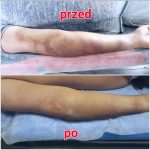

Plastrowanie dynamiczne likwiduje obrzęki limfatyczne poprzez poprawę krążenia krwi i chłonki, zmniejsza zatory tkankowe i stany zapalne oraz otwarcie drenażu limfatycznego pod skórą. Plastry pomagają również w korekcji stawów.